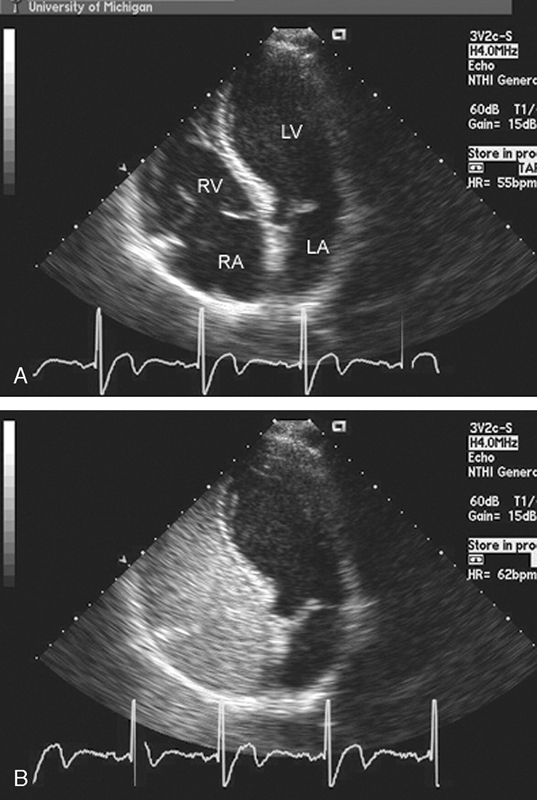

فحوصات تشخيصية لبعض امراض القلب والشرايين التاجية